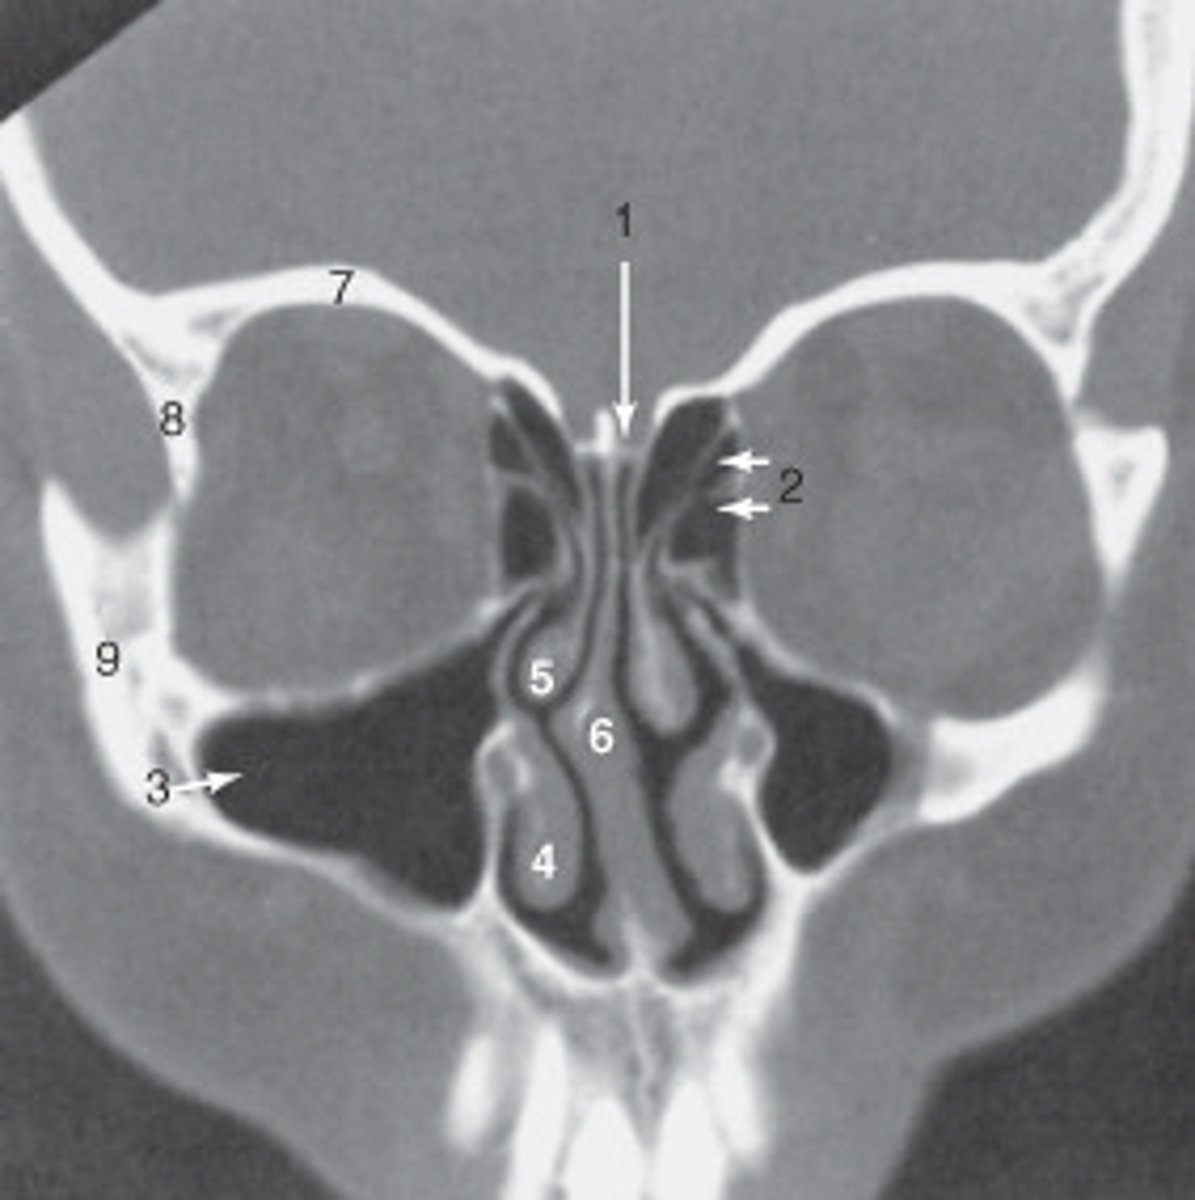

the nasal septum is labeled:

<p>the nasal septum is labeled:</p>

the zygoma is labeled:

<p>the zygoma is labeled:</p>

the lateral orbital wall is labeled:

<p>the lateral orbital wall is labeled:</p>

the structure labeled 3 is the:

<p>the structure labeled 3 is the:</p>

roof of the orbit

the structure labeled 7 is the: